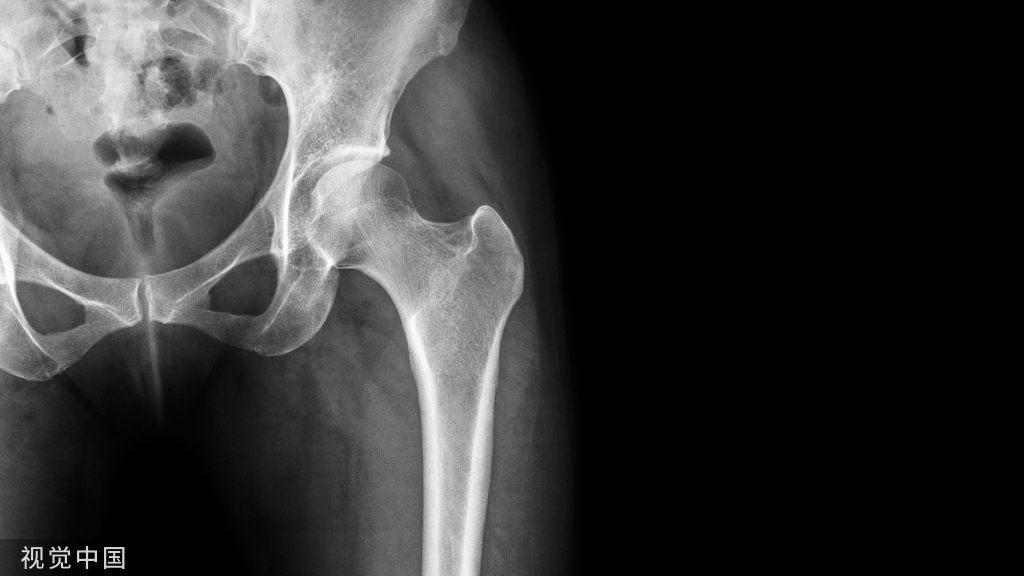

X 线平片和 MRI ,如果 X 线平片或 MRI 检查可见明显的皮质下骨囊肿,则可提示痛风石或骨侵蚀。在首次痛风发作时通常无法检出这些影像学改变。